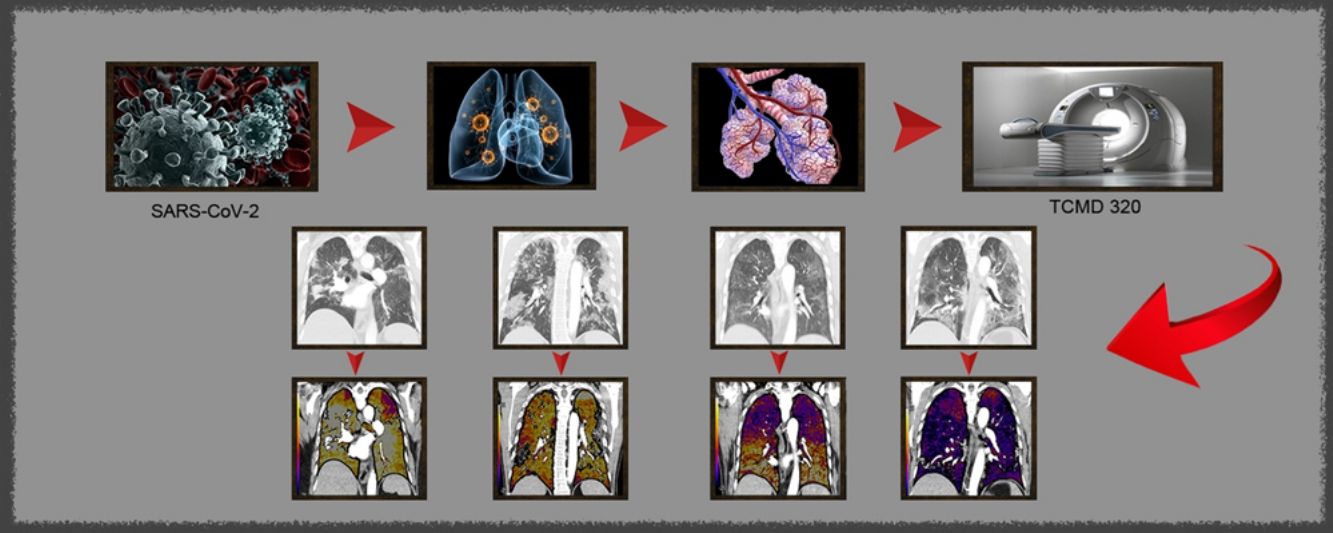

Paciente con COVID-19 con insuficiencia respiratoria grave a pesar de mejoría de parámetros inflamatorios.

Imágenes axiales de angiografía pulmonar con TC y mapa de yodo, con ventana de pulmón (A, C) en cayado y lóbulos inferiores y su correlación con las imágenes del mapa de yodo axial (B, D), coronales (E, F) y reconstrucción MIP coronal en ventana de mediastino (G, H).

Parénquima con moderada afectación parenquimatosa, con consolidaciones subpleurales parcheadas de predominio en lóbulos inferiores y extensas áreas de hipoperfusión (azules) parcheadas de predominio subpleural en el mapa de yodo, que se correlacionan con la falta de relleno del territorio vascular distal en el MIP coronal (flechas azules), sin TEP visible.